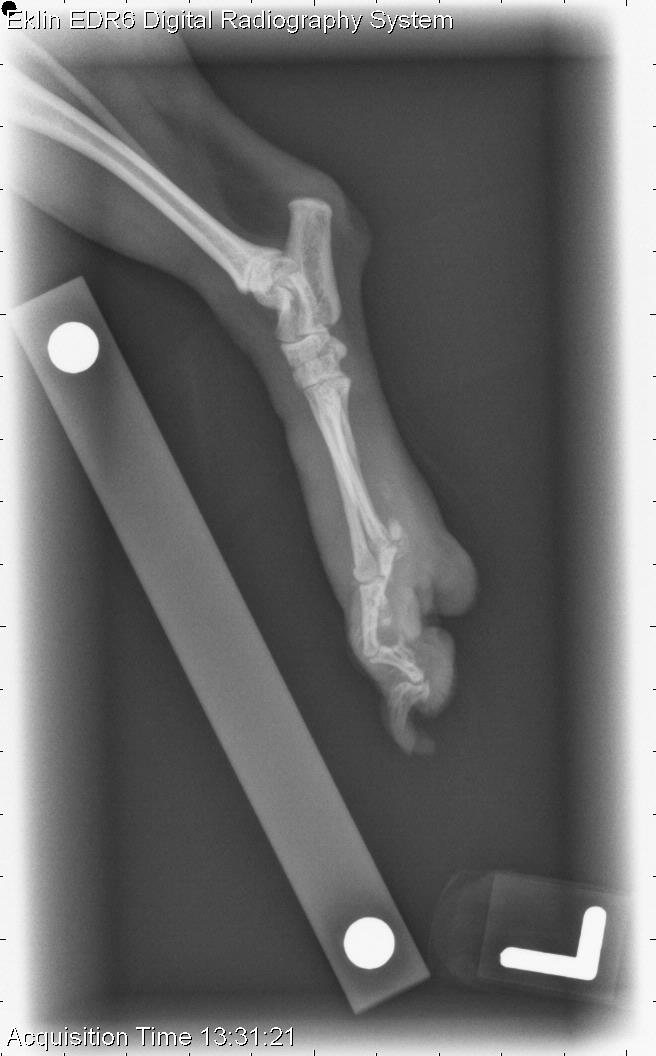

This week’s case is a 4-year-old female Yorkshire Terrier with a 2-year history of toe swelling with previous P2 amputation. For musculoskeletal cases, my first priority is to decide whether the lesion is aggressive or non-aggressive. What do you think?

On radiographs of the left pelvic limb, there is lysis of the second metatarsal bone with only a proximal remnant. The third digit, including P1-2 and the distal metatarsal bone, are also lytic. The regions surrounding the distal interphalangeal joint of P5 are also lytic. P4 appears intact. There are small fragments of soft tissue in the region of the lytic metatarsal bones. The soft tissues surrounding this region are thickened, and there is smooth periosteal reaction and sclerosis of the third and fourth metatarsal bones.

Severe multifocal aggressive bone lesions with osteolysis in the distal left pelvic metatarsal and phalangeal regions. This is most likely due to osteomyelitis; however, a soft tissue neoplasm invading bone cannot be completely ruled out.

The digits were amputated and osteomyelitis was found in P3, with resorption and fibrous replacement of bone in P5. No organisms were isolated.